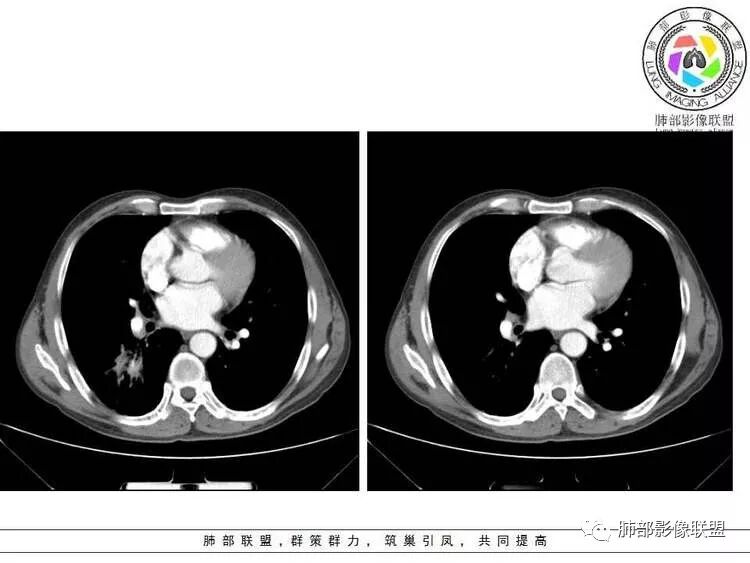

南边:紧贴着斜裂过来的一个病灶,它的特点是:外围大,内带小。它整个下叶背段体积与对侧相比稍微缩小一点,但是缩小地不是很厉害。外支朝前下走了,仔细看血管,肺动脉走行自然,直达远端。远端实变区是肉芽肿成分,稍微有一点低密度,没有明显坏死,稍微有一点点坏死。而且附近有很多卫星灶,附近很多斑片影,有一些明显有气道壁增厚,细支气管炎的特点,还有就是下叶其他段很多斑片状影。换个角度,第一如果是肺癌,刚才看到PET-CT提示肺癌伴阻塞性肺炎,这个是不符合的。第二如果是肺癌阻塞性肺炎,近端血管肺动脉走行不会那么自然集聚的,这个是不符合的。理由是:如果这个病灶是肺癌,那么明显属于中央型肺癌,中央型肺癌的特点是近端大,远端小,近端是一个肿块,远端阻塞,远端阻塞是阻塞性炎症或者不张,它应该体积缩小,斑片状实变,不会这么密实。刚才有老师提到支气管,这个片有缺陷的地方,给的图像好像那层,如果把其他图像拿开再重叠一下。

南边:这个肺门区,11区和7区都有一些淋巴结,淋巴结的形态不是类圆形,而是梭形的。这个病灶给的图比较少,个人倾向,第一强化非常均匀,肉芽肿性病变;第二,里面血管走行非常自然,远端大近端小,倾向炎性,特别是下面还有斑片状影,非阻塞远端,支气管远端病灶下叶背段,其他段也有,所以我倾向炎性;另外,它里面整个走行符合支气管树爬行征,我倾向结核可能,首先我定在炎性,其次有没有结核的可能。

轻度强化         PET-CT:SUV 7.5,高摄取